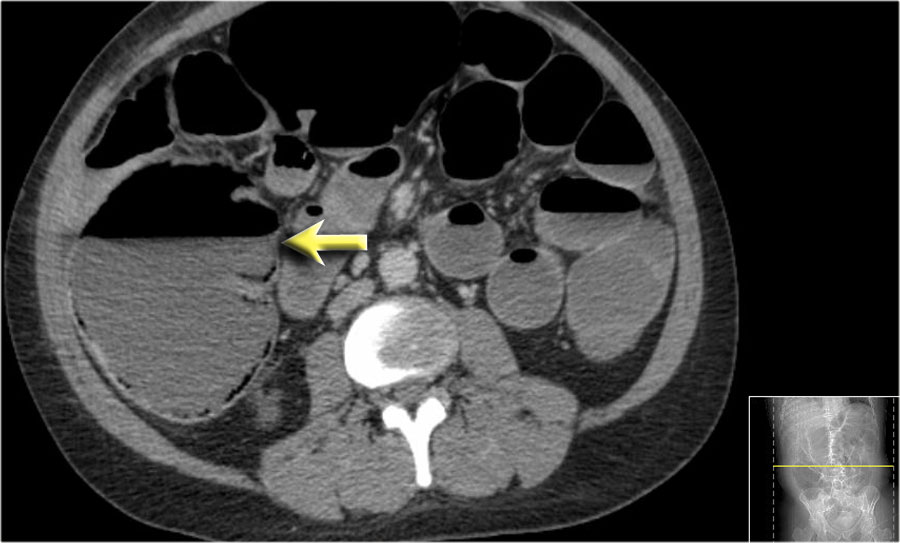

Một bệnh nhân khác với hình ảnh ruột thiếu máu cục bộ và phù nề mạc treo ruột lan rộng.

Trong phẫu thuật, toàn bộ đoạn ruột non này đã bị hoại tử.